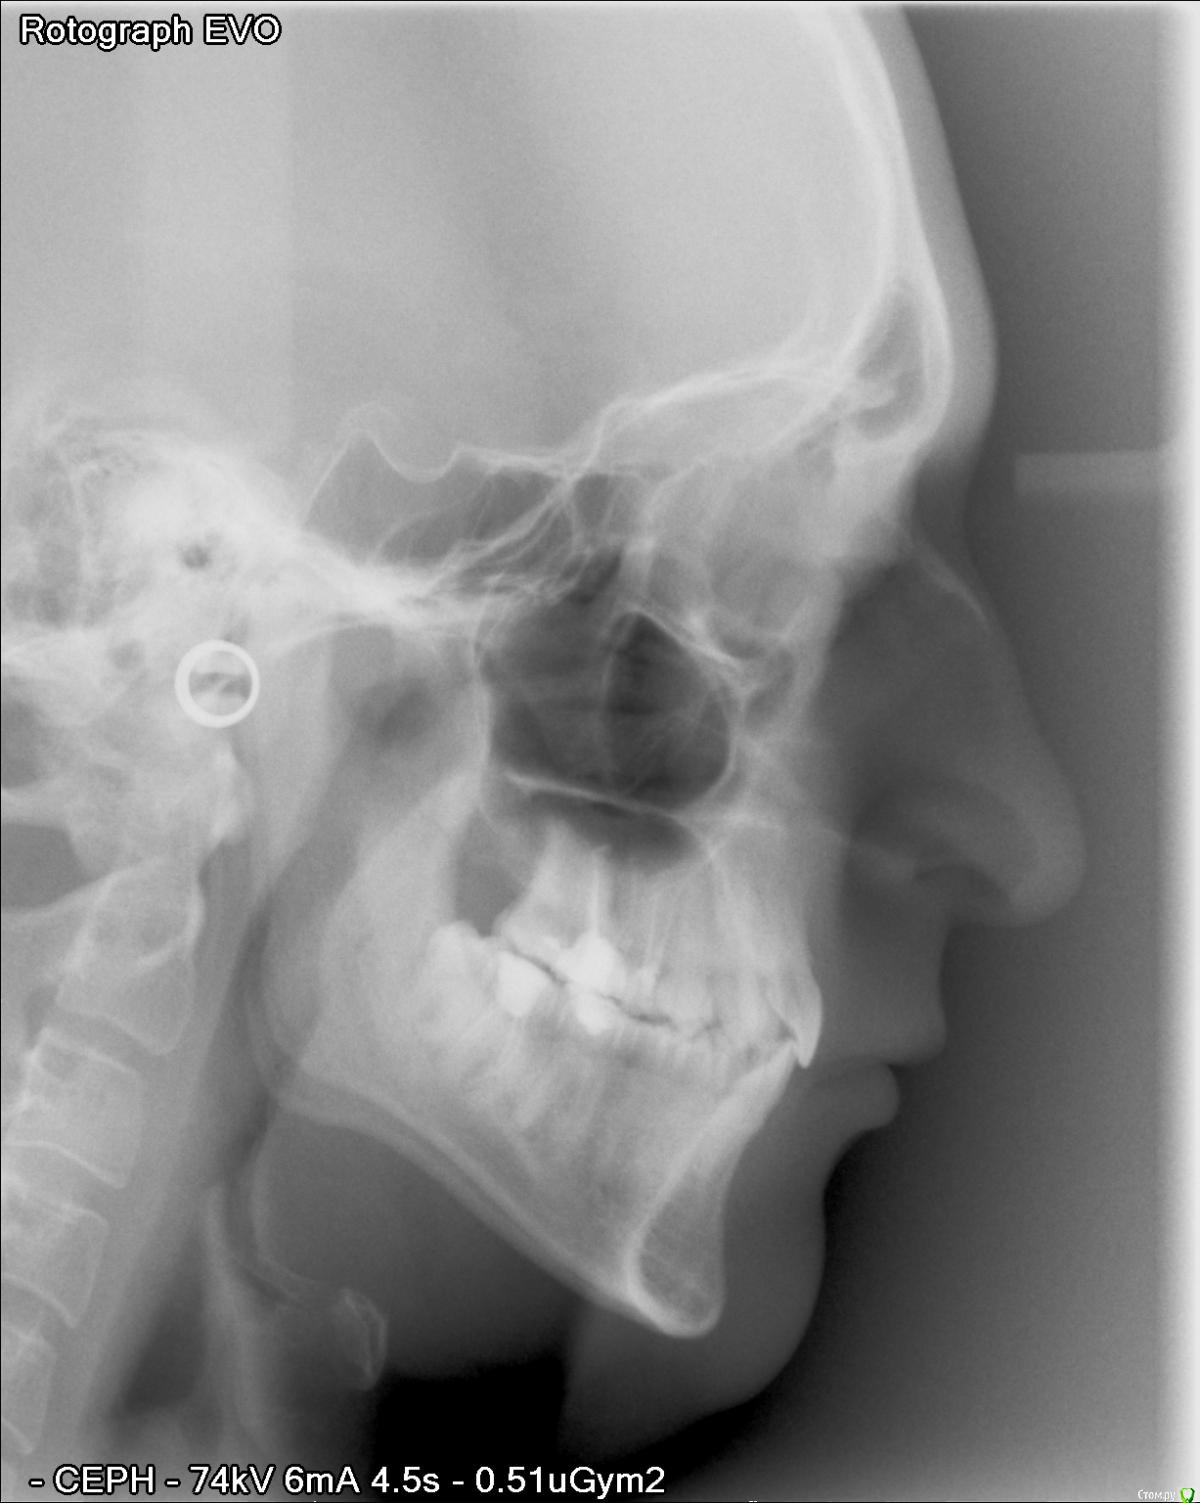

lc_ Опубликовано 22 декабря, 2015 Поделиться Опубликовано 22 декабря, 2015 (изменено) Здравствуйте, эксперты! Мне 27 лет, достаточно давно стоматологи советуют мне обратиться за ортодонтическим лечением. Аргументы приводятся в основном не в силу косметических соображений. 3 года назад я даже было согласился и удалил 2 верхние "восьмерки" (предложением было удалить все 4), но дело до конца не довел. После очередного посещения терапевта, вопрос снова был поднят. Итак, хочу обратиться за консультацией к независимым экспертам: стоит ли устанавливать брекет-систему? Ограничиться просто удалением оставшихся "восьмерок"? Не предпринимать никакие действия и дальше жить спокойно? Спасибо! P.S.Все фото не влезли. Поэтому боковые снимки:http://s020.radikal.ru/i709/1512/be/b7122505b8b3t.jpghttp://s011.radikal.ru/i318/1512/a3/27f5404deddct.jpghttp://s018.radikal.ru/i525/1512/c5/1e3523662a9at.jpghttp://s019.radikal.ru/i634/1512/b7/7bb11e619334t.jpghttp://s015.radikal.ru/i331/1512/45/4e6d94c5b833t.jpg Изменено 22 декабря, 2015 пользователем lc_ Ссылка на комментарий